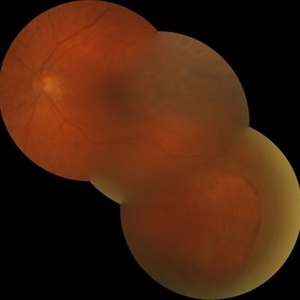

Outer Retinal Tear in Schisis-Detachment - Mosaic Photo

Large outer retinal tear in combined retinoschisis-detachment. The retinal vessels are visible going over the retinal break.

Photographer: Janice Neal, Gurley Eye Care Associates

Imaging device: Topcon Mark II

Condition/keywords: retinal tear, retinoschisis